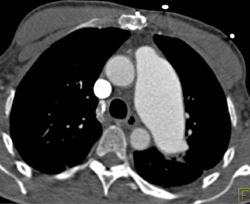

Pseudocoarctation